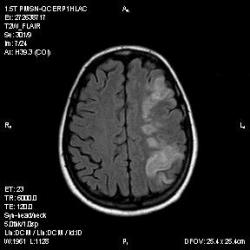

Из анамнеза - Женщина 45 лет. За год похудела на 15 кг (со слов матери), в последние месяцы случались эпизоды потери сознания. Онкозаболеваний и прочая в анамнезе нет. Сознание спутанное, из особенностей в анализах только подъем амилазы крови.

К сожалению, не владею методом КТ, но учитывая наличие неравномерного уплотнения в мозговых структурах с элементами очаговых "вкраплений", единственное, что приходит на ум - это рассеяный склероз. Хотелось бы уточнить, что беспокоило пациентку в течение последнего года кроме потери веса и эпизодов потери сознания? Была ли какая-либо очаговая неврологическая симптоматика? Отмечались ли какие-либо расстройства в двигательной или чувствительной сфере и т.д.? С уважением Helenmar.

И это точно не РС, т.к. характер очагов другой, ни один из них не копит контраст, нет субтенториальных очагов (извиняюсь, я этого в сообщении не указал), нет клиники.

"Раскрою" карты. Мы подумали о синдроме MELAS (mitochondrial encephalomyopathy, lactic acidosis and stroke) - дословно, митохондриальная энцефаломиелопатия, лактоацидоз и инсульт. В качестве дифференциальной диагностики можно было бы предположить вирусный энцефалит, но опять-таки, расположение очагов смущает - только с одной стороны и в абсолютно различных структурах.

В данном случае мы видим импульную последовательность FLAIR - режим с подавлением сигнала от воды, поэтому ликвор гипоинтенсивен, а также (вторая серия) - изображения, взвешенные по T1 после введения контрастного препарата. На T1 жидкость (ликвор) также представляется гипоинтенсивной. Зато на этих сериях гиперинтенсивны сосуды, т.к. контрастное вещество циркулирует в кровяном русле.

Изменения носят сосудистый характер. Процесс достаточно острый, имеется объемное воздействие, борозды левой гемисферы компремированы. По поводу MELAS синдрома очень сомневаюсь, почему поражена только левая гемисфера? Надо делать МР-ангиографию, смотреть нет ли стеноза

MELAS синдром - дебютирует с детских лет, характерен целый комплекс неврологических проявлений, заболевание генетическое, поражение системное, хотя есть множество вариантов митохондриального поражения, все же сомнительно. Хотелось бы акцентировать внимание, что гиперинтенсивные очаги есть в мозолистом теле, поражены выражено перивентрикулярные отделы, U -пути, белое вещество, поэтому так категорично демиелинизацию не вычеркивала бы из дифряда ( хотя тоже нетипично односторонее поражение). Думаю, для объективных выводов все же мало общей информации о пациентке, были ли клинические эпизоды раньше, чем объяснить такую потерю веса (возможно есть проявление паранеопластического синдрома?). Ну и МРТ-контроль в динамике, ангиография.

Да, неоднозначный случай. Точно не РС и не ОНМК. Я бы написала асимметричную лейкоэнцефалопатию неясного генеза. Можно было бы думать о лимфоме (полифокальное поражение, да еще мозолистое тело вроде бы задействовано (эх, сагиттальчики бы)). Но! Учитывая отсутствие накопления КВ.... Ну и надо исключать интоксикацию, всяческие аутоиммунные процессы (в т.ч. и васкулиты), сахарный диабет, ну и естественно наследственную патологию обменных процессов. УУУх! Вот.......

Имхо ишемический онмк в бассейне сма. Особенно показательны 5-й и 6-й файлы, отграничение как раз на границе бассейнов средней и перикаллёзной. Плюс одностороннее поражение.